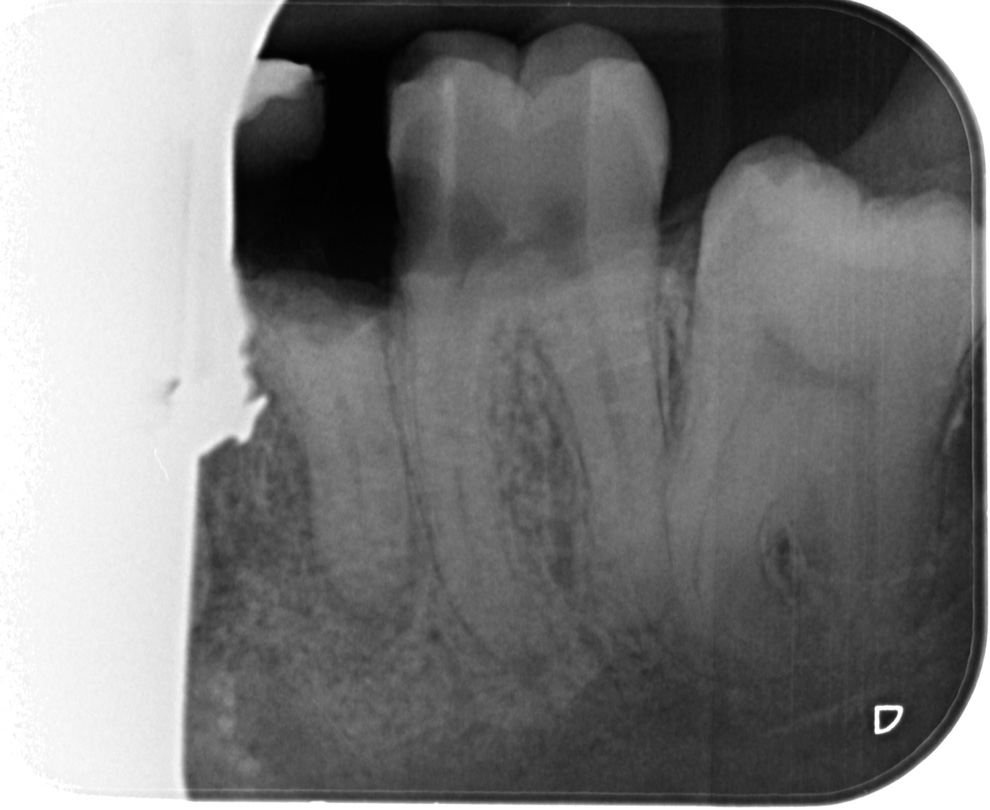

Ik voelde dat hij ook twee of drie boven tanden raakte . Dit is denk ik wel te zien daar het voor die doeleinde meer geen boor was , maar een frees was met een rond bolletje . De grote van de frees is ook goed te zien aan de tand erboven in mijn mond die hij beschadigd heeft .Ondnaks de verdoving voel je de triling van de boor Deze vulling is inmiddels er uit gevallen . Wat later werd de eerste foto gemaakt

Na enkele minuten werd er pas een tweede foto gemaakt omdat zoals de Bali assistente zei er stond op de eerste foto maar een tand.op

Toen hij klaar was zei hij dat het op de eerste foto nog kon ""kaakoverzicht foto"", Maar zoals hij zei op de foto die genomen is 21-10-2021 niet , dat snap ik ook wel de kies was net door hem weggefreest

Er is geen nieuwe foto tenminste geen begin foto gemaakt Element 36 is niet meer te behouden Deze foto is pas gemaakt nadat hij element 36 had weg gefreest en 37 was al geopend voor een wortel kanaal behandeling

Er zijn op de fotos ookop element 36 en 37 geen wortepunt onstekingen te zien

Toen ik zei dat het volgens mijn twee second opinions het de gewoonte was om detail foto te maken . Daarop zei de weledelgeleerde tandarts A Padrao dat hij dat ook had gedaan .Waarop ik zei dat hij dat had gedaan nadat de kies element 36 was weggefreest!!. Ook bij een second opinion zeg de betreffende tandarts:Hij kon er niets over zeggen er was geen beginsituatie . Daar waar het vraagteken staat er is geen beginfoto .